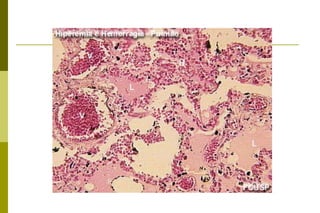

Hiperemia  passiva pulmonar

Congestão pulmonar passiva aguda caracterizada por pulmões pesados e úmidos, firmes e avermelhados. Este estado pode decorrer de distúrbios hemodinâmicos atribuíveis ao aumento de pressão hidrostática

Congestão pulmonar passivaaguda caracterizada por pulmões pesados e úmidos, firmes e avermelhados. Este estado pode decorrer de distúrbios hemodinâmicos atribuíveis ao aumento de pressão hidrostática